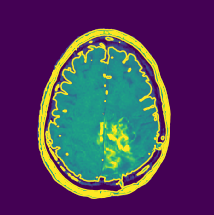

Visual inspection: An overview of the preprocessing for normal MRI can be seen in Fig. 10. The preprocessing for benign MRI can be seen in the Fig. 11 and malignant MRI can be seen in the Fig. 12.

To have a good demonstration of the preprocessing, three MRI images are considered, one is normal which is shown in Fig. 10(a), that is, without any neoplasm, the second one with benign neoplasm which is shown in Fig. 11(a) and the third one with malignant neoplasm which is shown in Fig. 12(a).The contour is plotted for three different MRI images, each for normal (see Fig.10(b)) , benign (see Fig.11(b)), and malignant (see Fig. 12(b)). Similar to contour, Sobel egdes are shown for the three MRI images: normal ()in Fig. 10(c)), benign (in Fig.11(c)), and malignant (in Fig. 12(c)). The final result after taking difference is shown for the three MRI images, normal (Fig. 10(d)), benign (Fig. 11(d)), and malignant (Fig. 12(d)).

Refer to caption

(a) Malignant GS

(b) Malignant CT

(c) Malignant SE

(d) Malignant SD

Figure 12: Proposed preprocessing applied over malignant MRI images.

Figure-12 shows a transition of the various stages of the proposed preprocessing for a malignant brain neoplasm. The contour of the malignant brain produces a centralized yellow region as seen in Fig. 12(b). But when compared with the difference contour, the less interesting regions are colored green with a brown border as previously seen with benign MRI. Further, a brown edge with yellow is is seen in the final image where the malignant neoplasm is present as seen in Fig. 12(d). The proposed preprocessing can outline the portion with the brain tumor effectively, even if the tumor is discreetly spaced. Further, many preprocessing techniques tend to over soften the image during the noise removal process to get better accuracy, but this changes the original image features. This proves to be beneficial when detecting the presence of neoplasm but during the classification of the severity, this process fails to get good results. But in the case of the proposed preprocessing, the final output MRI image is free of over softness and hence the features are preserved better.